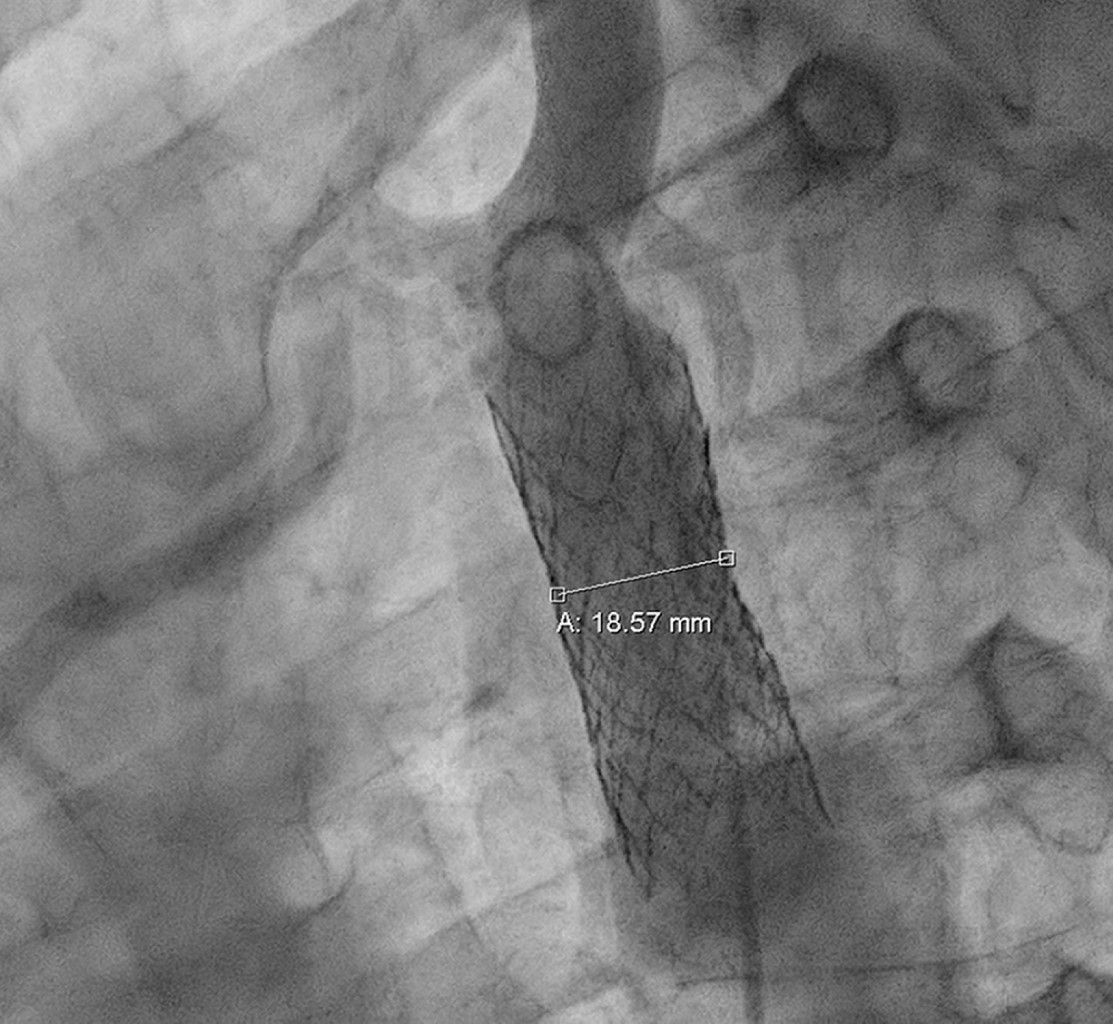

Coartación aórtica asociada a válvula aórtica bicúspide complicada con aneurisma aórtico postdisección

Sánchez-Amaya DJ, Godínez-Córdova LB, López-Lizárraga MÁ, Araiza-Garaygordobil D, Arias-Mendoza A

coartación aórtica, disección aórtica crónica, aneurisma aorta ascendente, válvula aórtica bicúspide.

La coartación aórtica es un trastorno congénito que afecta no solamente a la aorta, sino que también puede asociarse a válvula aórtica bicúspide y predispone a síndromes aórticos. Se reporta el caso de un paciente de 28 años de edad con hipertensión secundaria debido a coartación aórtica postductal asociada a válvula aórtica bicúspide que a su vez presentó disección crónica de la aorta ascendente. La coexistencia de enfermedad valvular aórtica, así como múltiples condiciones aórticas, es una situación rara que requiere una evaluación altamente especializada para garantizar un resultado favorable. El tratamiento se estableció en dos fases: aortoplastia con colocación de stent y luego cirugía de reemplazo aórtico y valvular, con una recuperación favorable.

Figura 4